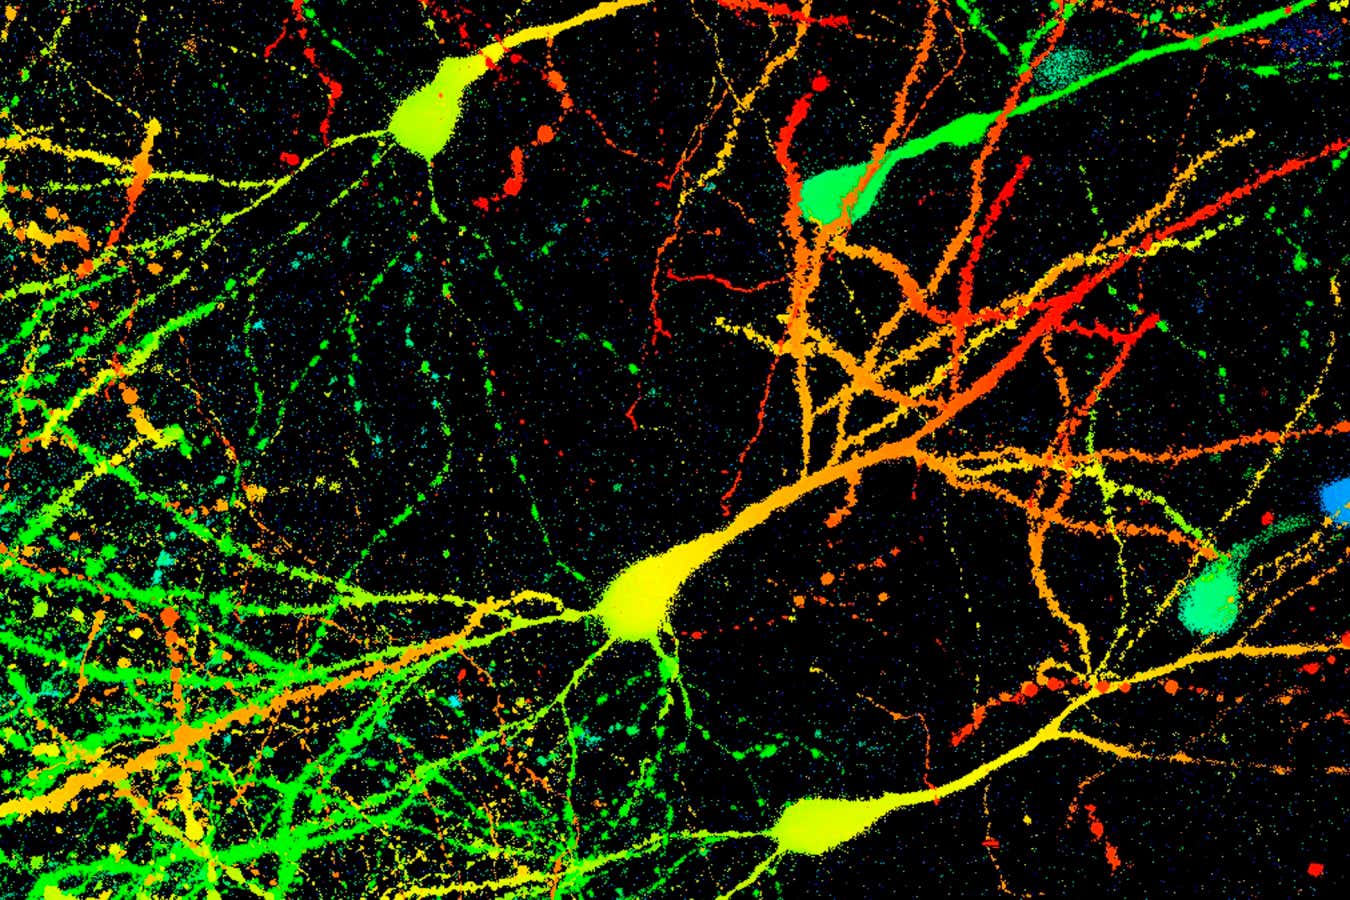

Parkinson’s occurs when nerve cells in the brain become depleted. This light micrograph shows mouse neurons labelled with a fluorescent protein to distinguish between cells at different depthsDR GOPAL MURTI/SCIENCE PHOTO LIBRARY

Parkinson’s occurs when nerve cells in the brain become depleted. This light micrograph shows mouse neurons labelled with a fluorescent protein to distinguish between cells at different depths